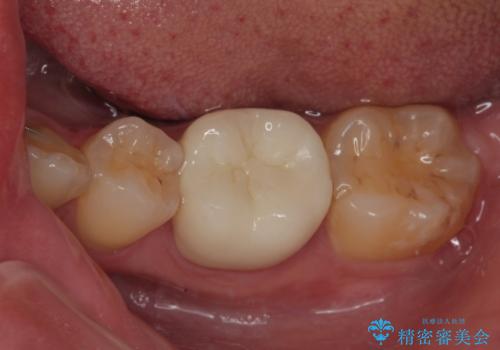

金属の詰め物が取れた オールセラミッククラウン

- メタルインレー(保険の金属の詰め物)が取れたとのことで来院された患者様です。

拡大鏡視野下にて、メタルインレーの範囲が大きく虫歯もあったため、オールセラミッククラウンにて修復を行いました。

型どりはシリコーン印象材にて型どりしています。

見た目、噛み合わせともに満足していただけました。